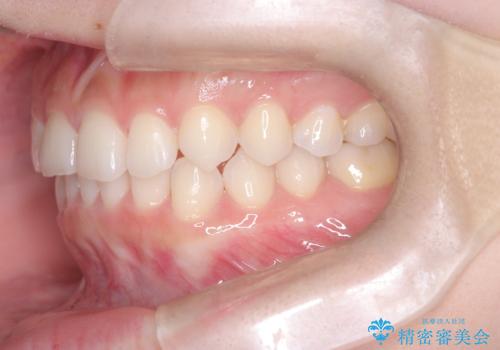

- 前歯のガタガタが気になるとのことでご相談いただきました。診察すると、歯列のスペースが不足し、前歯が重なっている状態でした。抜歯をせずに整えるため、歯と歯の間をわずかに削るIPR(歯列幅径削除)と、奥歯を後方へ動かす遠心移動を組み合わせてスペースを確保しながら並べる治療計画を立てました。

インビザラインを用いて歯を少しずつ移動させながら、IPRで微調整を行い、スペースを確保しました。また、奥歯を遠心移動させることで、前歯を自然な位置に並べることができました。治療後は、「ガタガタがなくなり、スムーズな歯並びになった」と患者様にもご満足いただきました。